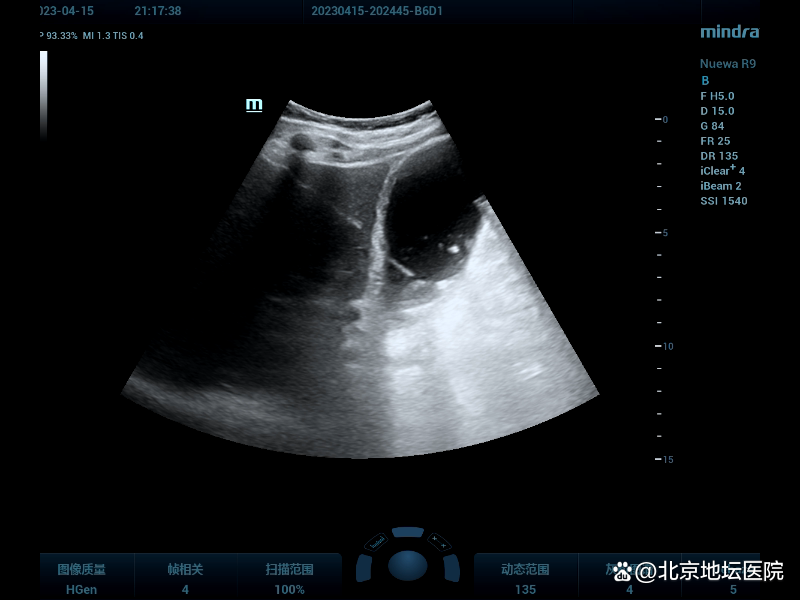

还记得入科不久,一个周六晚上,手机响了,是超声科马主任。原来是外科一名老年男性患者,胆囊颈部结石嵌顿伴急性胆囊炎,胆囊底部穿孔导致腹膜炎,腹痛剧烈。因血氧饱和度低,无法耐受急诊手术,需急会诊胆囊造瘘。赶到医院后,发现患者胆囊显著增大约126×48mm,张力大,因患者高龄合并多种基础疾病,急需胆囊减压。但患者腹痛伴有躁动,介入穿刺难度大,我与马主任共同商量并制定手术方案。常规消毒铺巾,局部麻醉,超声引导下8F猪尾管进入胆囊后,引流出墨绿色胆汁约 200ml,手术过程顺利。患者术前不适的症状立即得以缓解,紧锁的眉头慢慢舒展开,不停地说着谢谢医生。我心中的一块大石头终于放了下来。顺利完成来伊旗人民医院超声科的第一例独立完成的超声引导下胆囊造瘘术。